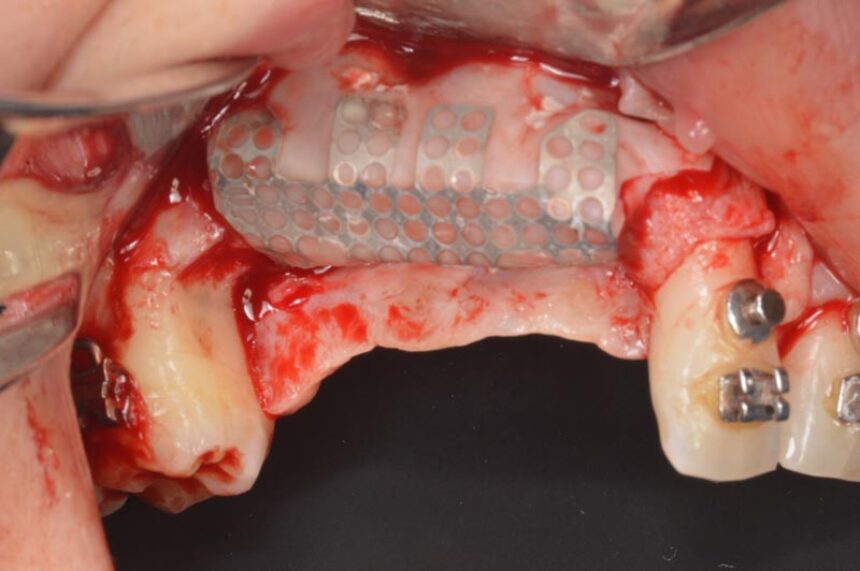

More specifically, ο Dr. Massimo Simion is one of the pioneers of the Guided Bone Regeneration procedure in the area of implant dentistry. Through his thirty-year experience, he will convey his experiences in this area, as well as the secrets of success in cases of extended deficit of the alveolar crest, in both the maxilla and the mandible, and he is going to present the management of various complications that may arise in handling such cases, which is a challenge for clinicians.

Horizontal and Vertical Ridge Augmentation: scientific background - surgical techniques – resorbable and non-resorbable membranes - bone graft harvesting from intra-oral sites – video

Management of GBR complications.